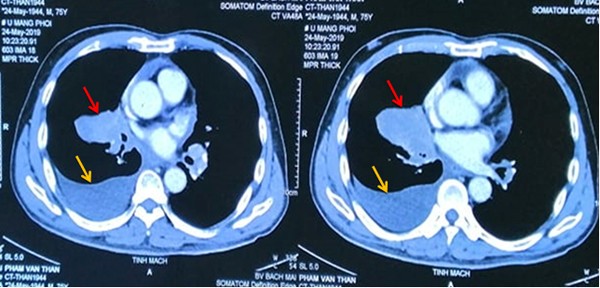

Đơn cử như trường hợp bệnh nhân Phạm Văn Thân, 76 tuổi mắc cùng lúc ung thư phổi di căn não, xương và ung thư tuyến tiền liệt giai đoạn muộn.

Do 2 ung thư đều ở giai đoạn muộn, bệnh nhân có rất nhiều hạch ở trung thất, hạch thượng đòn, tổn thương xương đa ổ. Khối u ở phổi đã to 6x4 cm, 3 khối u não kích cỡ 0,5-0,7 cm, u tuyến tiền liệt to gần 3 cm.

Dù bệnh nhân tuổi cao nhưng sau 3 tháng, kết quả điều trị rất tốt, bệnh nhân đỡ khó thở, đỡ đau đầu. Sau 9 tháng, ông Thân hết khó thở, không ho, không đau tức ngực, tăng 3kg, hết tiểu khó, khối u ở phổi xơ hoá, khối u trên não biến mất, khối u tuyến tiền liệt giảm còn 2 cm.

May mắn, bệnh nhân đáp ứng rất tốt với thuốc ngay ở bước 1 nên khối u phổi xẹp nhanh và bệnh nhân được xạ trị não kịp thời, giải quyết nhanh các ổ di căn não.